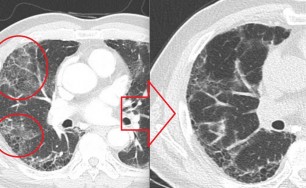

측농증

호흡기 질환만 연구, 숨케어한의원